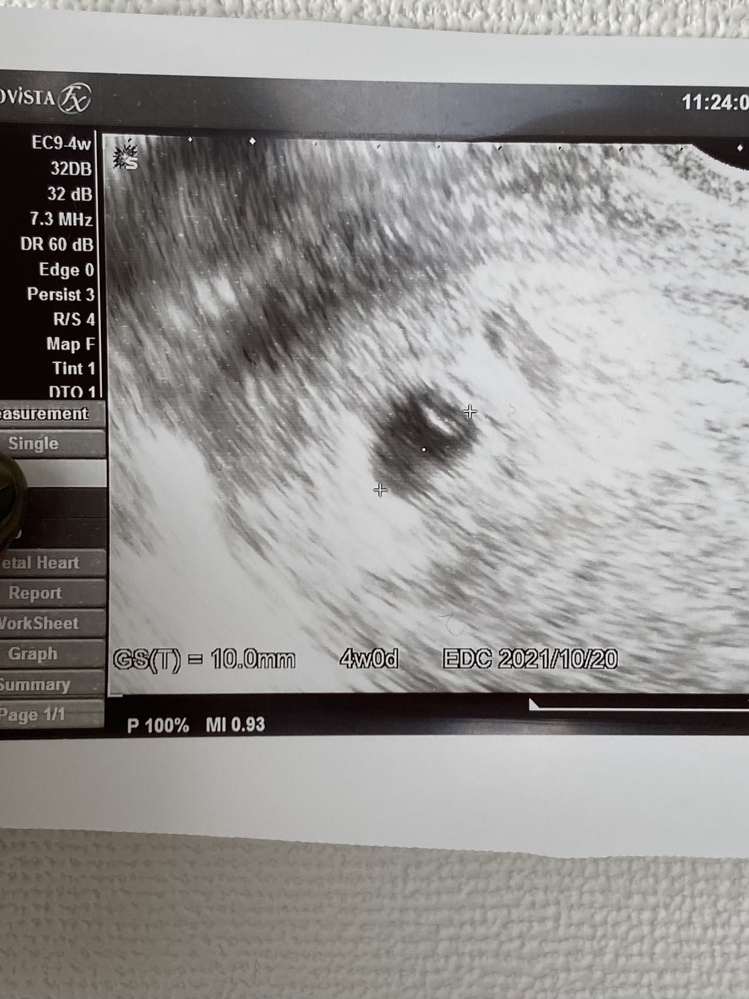

妊娠初期エコー写真について閲覧ありがとうございます。先日、病院を

エコー写真の見方(2D~4Dエコー)を知ると楽しみ倍増!│BABYDOT